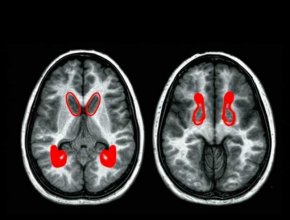

Дълго време се смяташе, че човешкият мозък спира да произвежда нови нервни клетки след детството. Нови изследвания обаче опровергават това убеждение и показват, че процесът на неурогенеза — създаването на нови неврони — продължава и в зряла възраст. Учените са открили активни клетки-предшественици в хипокампуса — зоната, отговорна за паметта и ученето, дори при хора на 70 и повече години.

Според проучвания, публикувани в Scientific American и Nature, тези нови неврони играят ключова роля за когнитивната гъвкавост и адаптивност на мозъка. Физическата активност, интелектуалната стимулация и здравословната диета се посочват като фактори, които могат да подпомогнат растежа на нови мозъчни клетки.

Въпреки че процесът все още не е напълно изяснен, откритието дава нова надежда за лечение на заболявания като Алцхаймер и депресия. Учените подчертават, че стимулирането на мозъка чрез учене и движение може не само да забави когнитивния спад, но и реално да помогне мозъкът ни да расте — дори след 50-годишна възраст.